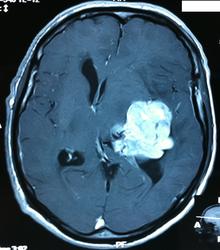

Начало вот здесь http://www.radiomed.ru/cases/kt-gms-obemnoe-obrazovanie-levoi-gemisfery-bolshogo-mozga-vnutrizheludochkovaya-meningioma. Пациент оперирован (меня сначала дезинформировали по поводу операции), перед операцией состояние ухудшилось, возникла правосторонняя гемиплегия, которая осталась и после декомпрессии. МРТ, КТ снимки и выписку предоставила супруга пациента, снимал на iphone, простите за качество, дисков с исследованиями не записывали. Надеюсь вопрос по данному случаю исчерпан.

Вот "цветочки":

T1+C

И Вы считаете, что эта опухоль имеет интравентрикулярную локализацию?

Изначально по КТ я так предпологал, а теперь на 100% уверен, разве МРТ это не показало? Гистологически - менингиома, опухоль мозговой оболочки. Покажите, пожалуйста, образование где-нибудь прилежит к костям, где есть мозговая оболочка? Я не вижу, зато отчетливо вижу в левом боковом желудочке из оболочек сосудистого сплетения. Что вас еще смущает? По-моему, предостаточно фактов, чтобы развеять все сомнения.

Мне видится так. Иначе в данной локализации просто неоткуда расти оболочечной опухоли. На контрольной КТ, после декомпрессии, когда срединные структуры стали действительно срединны, правое обызвествленное сосудистое сплетение видно отчетливо, а левое, где оно? Ведь если бы образование компремировало, то после операции, когда часть мозга пролабировало в трепанационное отверстие мы бы увидели и левое сосудистое сплетение, но оно интимно связано с образованием и даже "потянулось" за ним в сторону декомпрессионного отверстия, потому что это и есть "росток" откуда выросла опухоль.